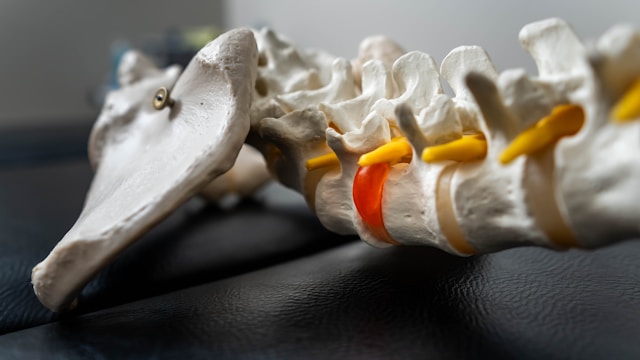

신바로정은 한방 병원에서 전통적으로 내려오던 관절 처방을 현대적으로 재정립한 전문의약품입니다. 수많은 약재 중 효과가 검증된 5가지 약초를 선별해 기초 연구, 전임상, 임상 시험을 모두 통과한 제품입니다. 주로 허리 디스크, 관절염, 근골격계 통증 치료에 처방됩니다.

두충은 뼈와 인대를 강화하고 허리와 무릎 통증에 오랫동안 사용되어 온 약재입니다. 신바로정에서 관절과 척추를 구조적으로 지지하는 역할을 합니다.